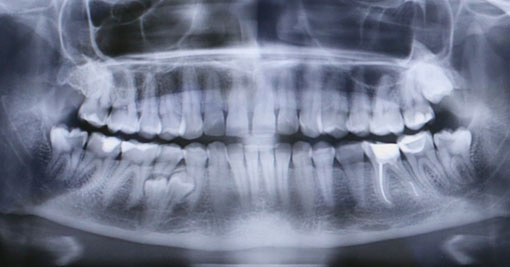

У моей пациентки мы случайно обнаружили два ретинированных сверхкомплектных премоляра:

При этом, весь комплект зубов на месте (за исключением правой верхней восьмерки — мы убрали её раньше).

Вот разбор снимка: